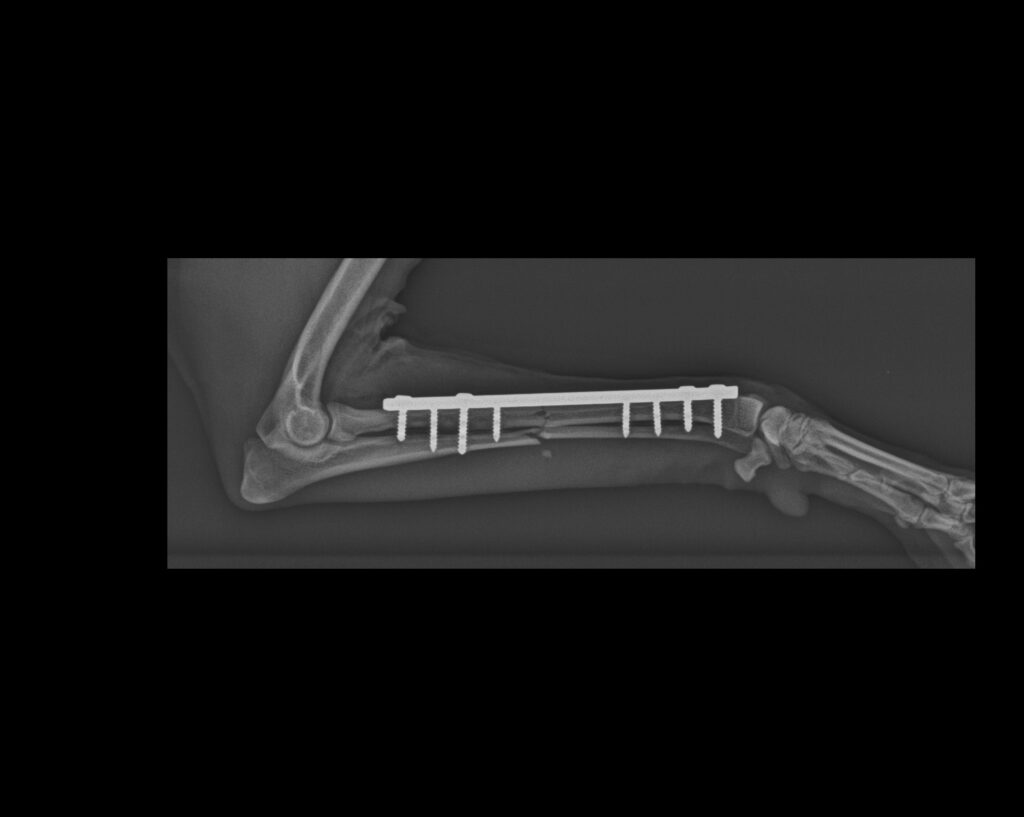

Panartrodesis de carpo